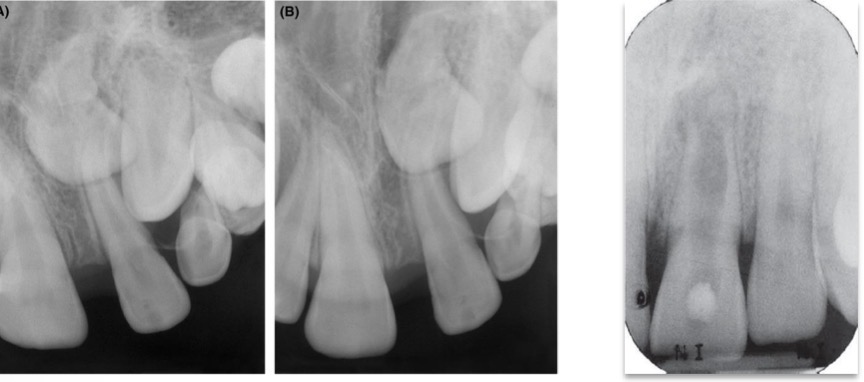

What’s this?

Germination

Fusion